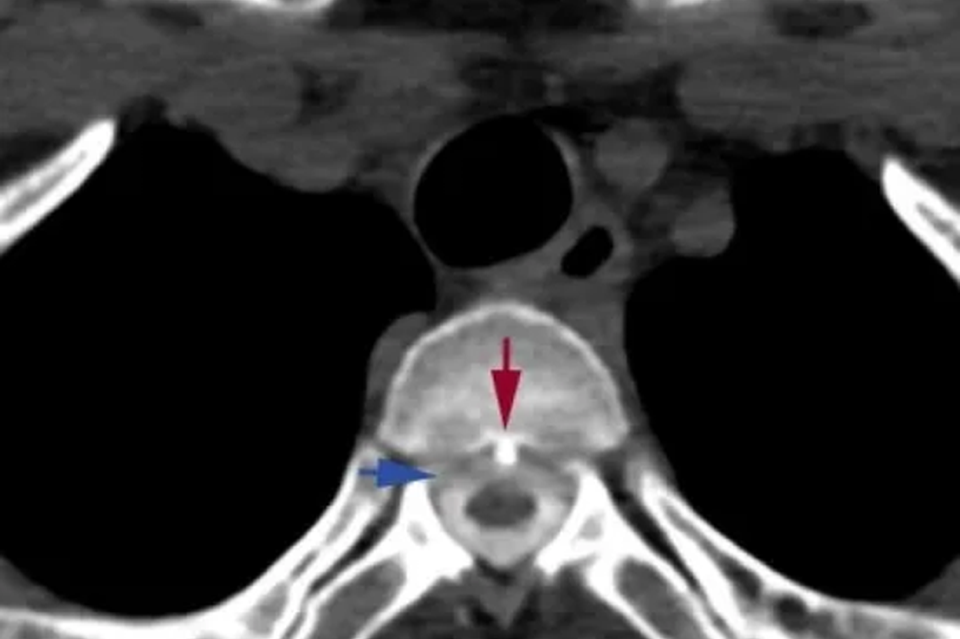

杭州72岁大爷急性心梗 心跳骤停20分钟最终死里逃生